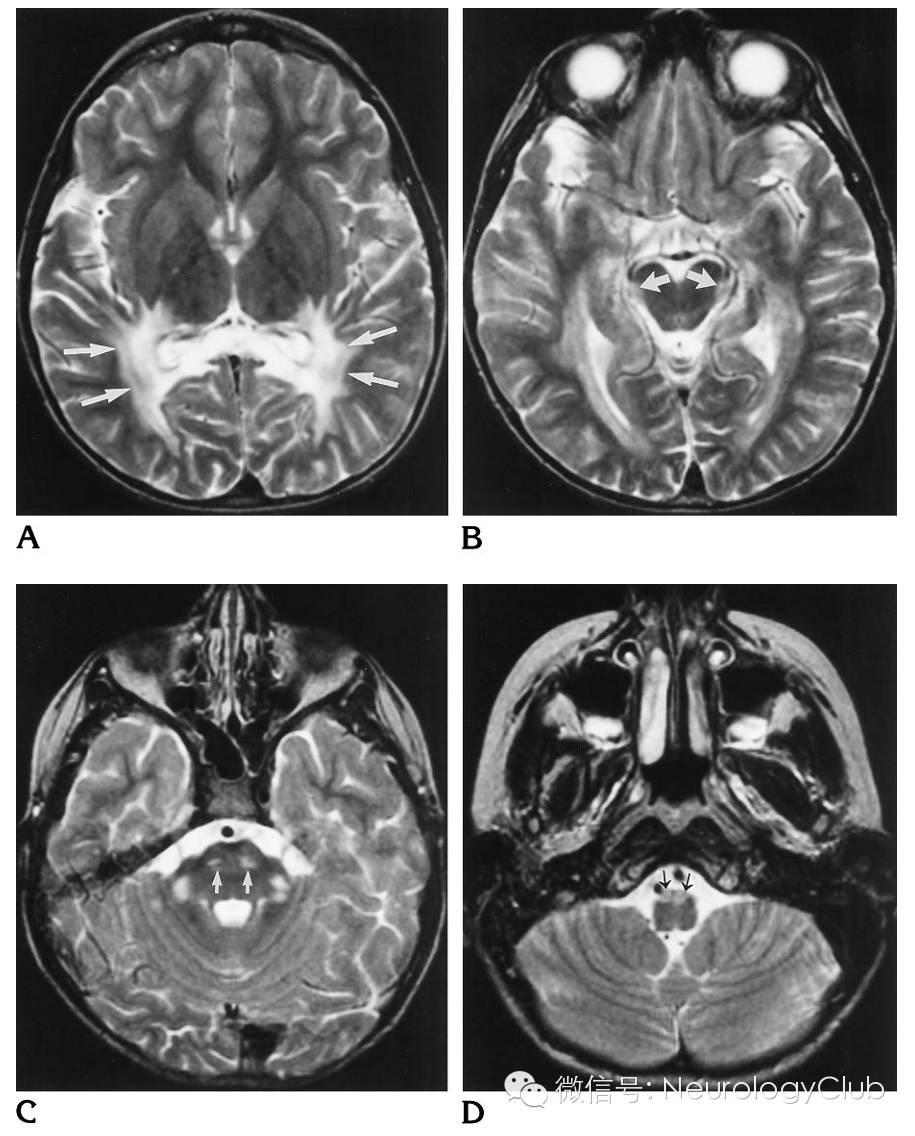

(8岁男孩,行为能力下降。A:T2WI可见胼胝体和脑室旁枕叶白质病灶,向前延伸至内囊和外囊;B:T2WI可见中脑水平大脑脚外侧高信号;C:T2WI可见脑桥水平双侧皮质脊髓束和小脑中脚高信号;D:T2WI可见延髓水平延髓锥体高信号)